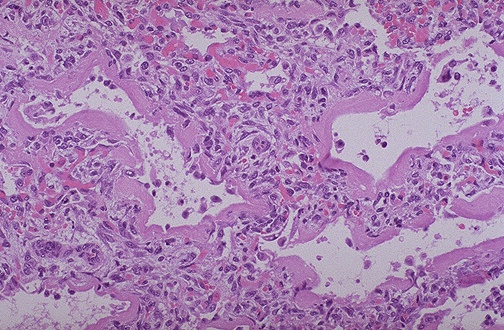

Image 4.1

The lungs are shown here? What do you see?